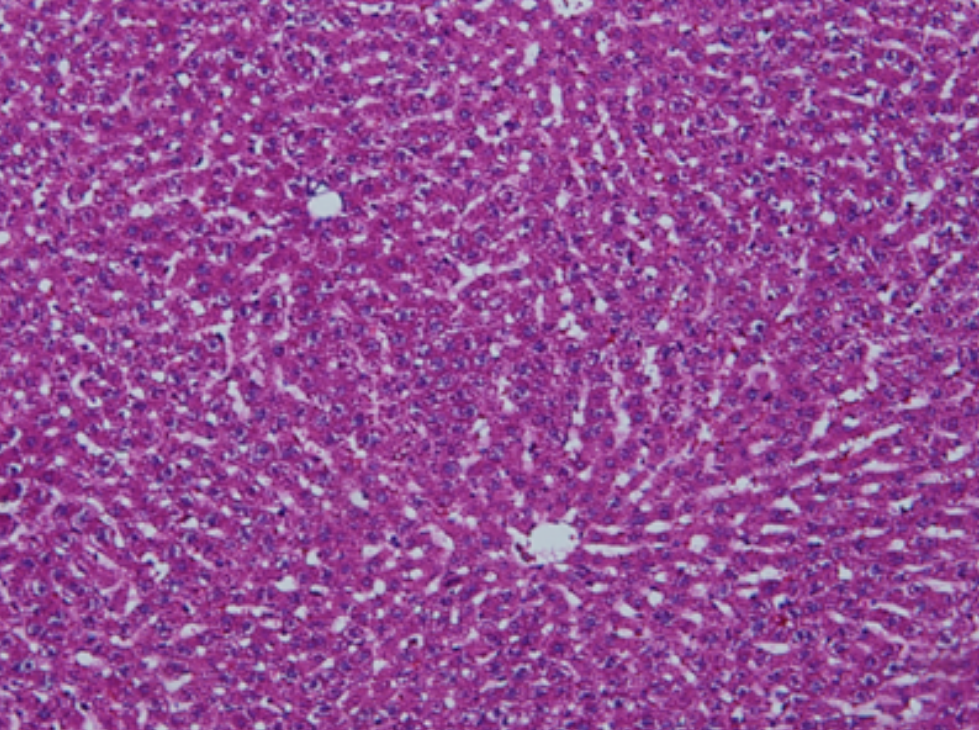

虽然HE染色是最常见且最基础的染色技术之一,😭但在实验过程中,很容易出现各种情况导致染色切片质量参差不齐。所以,小编根据以往实验经验,给大家整理归纳出了15个HE染色中的常见问题,还包含问题原因分析以及解决方法哦~

形成原因:切片经梯度乙醇处理后没有完全脱水,导致二甲苯透明、中性树胶封固后残留大量水分。 解决方法:首先移去盖玻片,用二甲苯溶解封固剂如中性树胶,再将切片置入无水乙醇内,待切片重新脱水完全后,用二甲苯透明处理,中性树胶封固。要注意所有用于脱水和透明的液体,在使用一定时间后,应及时更换。 二、细胞核呈红、棕色 形成原因:苏木精染色液过度氧化,切片在苏木精染液染色后返蓝不足。 解决方法:每次染色之前检查苏木精染色液的染色能力,发现苏木精染色液氧化过度应及时更换。此外,切片经苏木精染色后,要给切片以足够的蓝化时间,蓝化过程可用流水、温水、弱碱性溶液(如稀氨水或0.2%碳酸氢钠)等处理。 三、切片在脱蜡后出现大片白色斑点 形成原因:由于烤(烘)片温度太低,切片上的组织蜡膜在脱蜡前没有充分烤(烘)融化。或是因为切片在二甲苯液中停留时间不足,或二甲苯使用过久,造成的脱蜡不彻底。 解决方法:若是由于切片烤(烘)温度低所致,可以先用二甲苯去除切片上的封固胶,然后重新用二甲苯脱去切片上的石蜡,再进行后续染色。若是由于切片在脱蜡的二甲苯中停留时间不足或脱蜡二甲苯使用过久浓度不足所致,则需将切片退回到二甲苯中,停留较长时间,或更换二甲苯液体重新脱蜡,再入乙醇重新脱二甲苯,入0.5%盐酸水溶液褪色后,重新HE染色。 四、细胞核苍白暗淡,即苏木精染色太淡 形成原因:切片在苏木精染色液停留时间太短;苏木精染色液过度氧化,失去染色能力,不能再继续使用;分化步骤处理时间过长;固定不及时。此外值得注意的是,若骨组织细胞核暗淡,大多是脱钙过度造成的。 解决方法:切片重新染色。如果组织在酸性固定液(如Zenker、Bouin)或非中性缓冲甲醛液固定时间过长,细胞核染色能力将减弱,需增加其在苏木精染色液的时间,或用一些方法增加组织的嗜碱性,以改善细胞核的着色。例如,上述组织玻片可以使用Weigert铁苏木精染色液。如果组织是用Zenker液固定的,可将切片脱蜡后放在5%碳酸氢钠溶液3~4h,流水冲洗5min后染色。如果组织是用Bouin液固定的,可将切片脱蜡后放在5%碳酸锂1h,流水冲洗10min后染色。 五、细胞核过染,苏木精染液占据了细胞质 形成原因:玻片在苏木精染色液停留时间过长,或是切片太厚、分化步骤时间太短。 解决方法:如果不是因为切片太厚(用显微镜仔细上下微调,只有一二层细胞核层次),就需将切片进行脱色、漂白、重新染色,适当调整染色和分化时间。但如果确定是由于切片太厚导致的细胞核过染,则需要重新切片。 六、伊红着色淡 形成原因:可能是伊红染液pH值大于5,也可能是蓝化液残留过多,切片太薄,或是切片经伊红染色后在乙醇脱水时间过长。 解决方法:检查伊红染液pH值,必要的话,用乙酸将其调节在4.6~5.0之间,从而使伊红染色色彩艳丽。此外,确保每次蓝化步骤完成后,使用的弱碱性溶液被充分洗去,玻片上没有残留的弱碱性溶液。最后,检查切片的厚度,且脱水时不要让切片在低浓度乙醇中停留时间过长,因为含水多的低浓度乙醇会将切片伊红的颜色分化掉。 七、细胞质过染、分色不足 形成原因:伊红染色液浓度太高,特别是存在焰红燃料、四溴四氯荧光素钠。切片在伊红染色时间过长,或是切片在伊红染色后经乙醇脱水步骤时时间太短,而使乙醇分化伊红的作用不能产生,都能够使细胞质过染。 解决方法:适当稀释伊红染色液,减少伊红染色时间,或使切片在乙醇脱水等步骤时,停留时间相对均匀。同样,也要检查切片的厚度是否合适。 八、切片中出现蓝黑色沉淀物 形成原因:苏木精染色液中的金属膜黏附在玻片上。 解决方法:染色前仔细过滤苏木精染色液,建议使用半氧化苏木精染色液,如Gill苏木精染色液,可以避免过多的金属膜产生。 九、光镜下切片某些区域难以聚焦 形成原因:盖玻片上可能有封固切片的封固剂。 解决方法:移去盖玻片,重新用干净的盖玻片封片。检查切片封片方法,是人工手工封法,还是机器自动封法,如有问题及时调整。 十、封固剂从盖玻片与载玻片之间的缝隙回缩 形成原因:盖玻片弯曲或不平整,或是封固剂含二甲苯过多,稀释过度。 解决方法:移去盖玻片,重新找一张盖玻片,用干净的封固剂封片。如用手工封片法,保证在封固结束时,封固剂容器盖子为紧闭状态。且尽量使用小的容器盛装封固剂,一旦封固剂太黏稠,就可以选择废弃。 十一、细胞核呈灰蓝状态 形成原因:可能由于组织处理温度过高、过热,在液体石蜡中停留的时间过长。或是固定时间太短后,直接在高浓度的乙醇中进行了脱水处理。 解决方法:理论上来说,仅在组织浸蜡步骤才进行加热,组织不能在热蜡液中停留太久。如果由于某些原因不能进行下一步包埋处理,可将组织连同塑料包埋盒一并放置在室温空气中,冷却凝固,以备包埋。待需要包埋时再重新加温直至石蜡融化即可。组织在处理前必须确保固定良好,脱水最好能从低浓度的乙醇开始。 十二、类色素的点状结晶和黑色光滑细胞核 形成原因:这种裸核改变是因为切片封片前放置在空气中的时间太长,以至于二甲苯挥发,切片干燥。 解决方法:移去组织切片上的盖玻片和封固剂,重新处理。将切片水洗数分钟,然后重新脱水、透明、封固。封片过程中要保持组织切片的轻度湿润,尽量不要让其干燥。 十三、染色过淡或过浓 解决方法:如果染色过淡,可以增加染色剂的浓度、延长染色时间或更换新鲜的染色剂;如果染色过浓,则应减少染色剂的浓度或缩短染色时间。 十四、切片出现叠加褶皱 形成原因:新购买的玻片洁净度不够、用镊子撑开切片时操作不够熟练未能平整伸展,或玻片表面有油脂,切片粘贴不牢。另外,烤片时间不足、烤片温度过低或切片过厚造成切片脱落,都会造成重叠或有皱褶的情况。 解决方法:新购买的玻片最好能用硫酸清洁液浸泡一晚,然后流水冲洗干净。在适宜的温度下烤片时间宁长勿短,保证有充足的烤片时间和温度。另外,切片刀要锋利,才能切出厚薄适宜的切片,保证切片不会因为过厚而脱落。 十五、组织残缺不全或有刮划痕迹 形成原因:组织残缺不全是由于切片时修整蜡块时深度不够、组织没有全部暴露于切面。切片的刮划痕迹是由于切片刀的刀锋有缺口、包埋的组织有异物,或是钙化组织、骨组织及包埋石蜡有沙粒造成的。 解决方法:修整蜡块时保证组织块全部暴露于切面,切片时保证切片刀的锋利没刀口。同时在组织取材时去除手术异物和钙化组织。最后,骨组织要完全脱钙,这样可以保证切片的完整和平整美观。 *注:由于实验中导致结果出现误差的原因多种多样,以上内容仅供参考,具体根据实际情况进行判断。